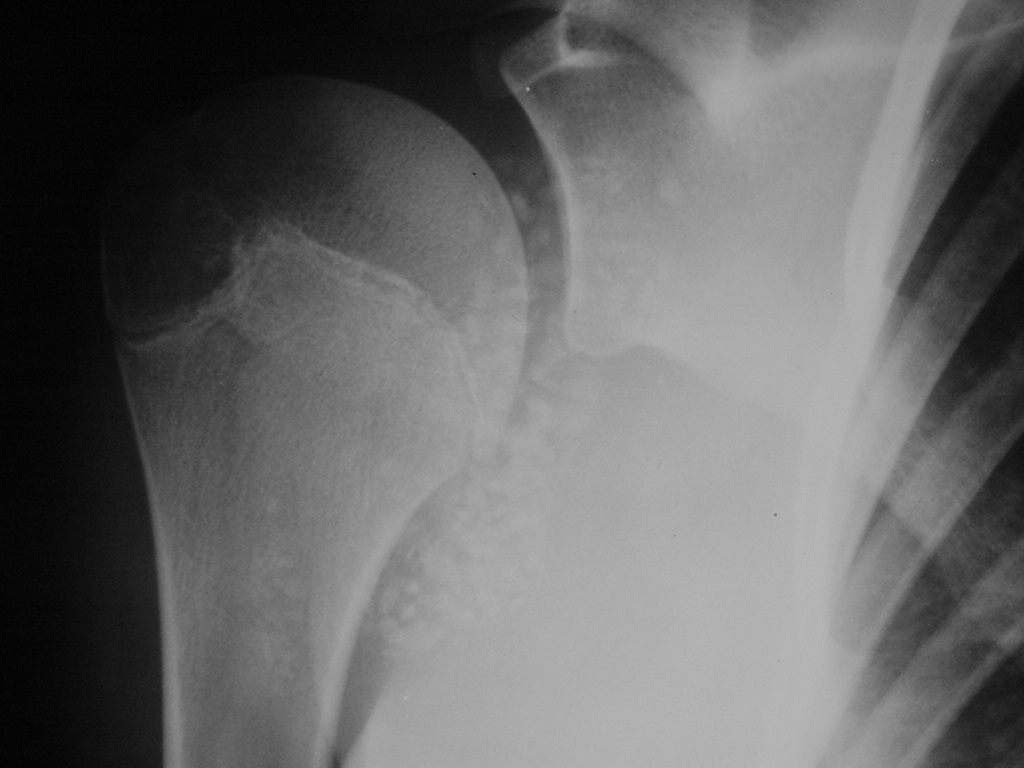

Synovial chondromatosis is an uncommon, benign, process that occurs in large joints, such as the knee (50%), hip, elbow, or shoulder. This process mainly affects synovium and hence most commonly arises from joints and tendons which are lined by synovium. Synovial Chondromatosis may also affect bursae and extend into surrounding soft tissues. This condition is seen in patients between 20 and 50 years of age and most commonly in men (male-female ratio of 2-4/1). The patient usually complains of pain, stiffness, crepitance, swelling, and joint locking. The knee is the most common site to be affected. Symptoms are long-standing and progressive. The plain x-ray may be normal (5 to 33%) or there may be small flecks of calcification (Fig. 1 & 2). On MRI the nodules of cartilage are easily seen. MR imaging may also show synovial thickening, joint erosions and intraarticular calcifications. The signal characteristics of these intraarticular bodies depend of their composition. If mineralization is not present the signal intensity follows the cartilage signal with intermediate signal on T1 images and high signal on T2 weighted MR images. Uniformly calcified bodies follows bone density on all sequences with bone marrow signal centrally and low signal peripherally (Fig. 3-5). Histologically the cartilage is arranged in nodules, which are quite cellular (Fig. 7-9). Synovial lining is present surrounding the cartilage nodules (Fig. 8). The cartilage nodules are often referred to as loose bodies however they are not really loose and embedded in the synovium lining. This is considered a metaplastic condition as opposed to a true neoplastic condition. Rarely it may turn into a malignancy usually a low grade chondrosarcoma. Malignant change is suggested by deep erosions into adjacent bone.

Fig. 1 & 2. Plain X rays of right shoulder synovial chondromatosis. AP (Fig. 1) and outlet (Fig. 2) views demonstrate multiple calcified bodies. Joint erosions are not seen on these x rays.